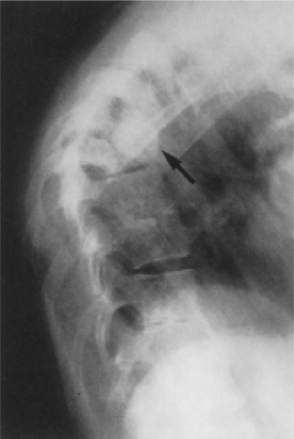

In the spine, surgery is more often needed to address nerve compression or deformity secondary to collapse of the vertebral body rather than the infection. The resultant deformity often includes a marked kyphotic curve with a gibbus formation (Fig. 25-4). Paralysis can be a serious complication of vertebral TB and can be a result of the disease process or a secondary spinal deformity. Paralysis persisting longer than 6 months is unlikely to improve, and late paralysis with inactive disease and significant kyphosis is much less responsive to treatment.70

Figure 25-4 Tuberculous spondylitis. Involvement at multiple levels. Gibbus deformity is seen in the upper thoracic region (arrow). (From Yao D, Sartoris D: Musculoskeletal tuberculosis, Radiol Clin North Am 33:681, 1995.)